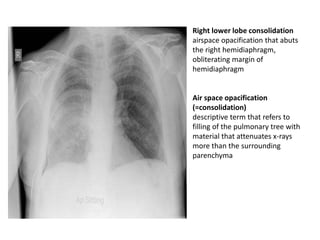

Right lower lobe consolidation

airspace opacification that abuts

the right hemidiaphragm,

obliterating margin of

hemidiaphragm

Air space opacification

(=consolidation)

descriptive term that refers to

filling of the pulmonary tree with

material that attenuates x-rays

more than the surrounding

parenchyma

Right lower lobeconsolidation airspace opacification that abuts the right hemidiaphragm, obliterating margin of hemidiaphragm Air space opacification (=consolidation) descriptive term that refers to filling of the pulmonary tree with material that attenuates x-rays more than the surrounding parenchyma